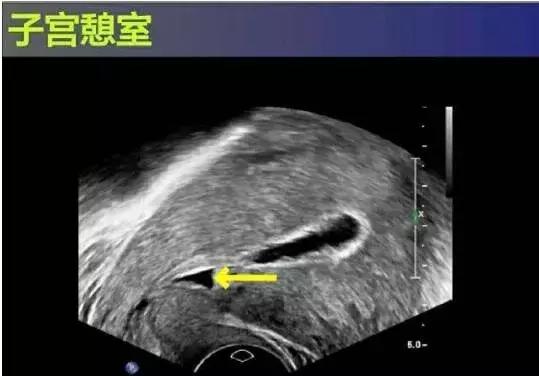

3. B超检查

子宫前壁下段存在宫腔内凸向浆膜层的锲形缺损,对缺损区进一步观察显示存在积雪,同时边界模糊,内部透声性较差,并且回声区肌层较薄,宫腔内膜线中断。